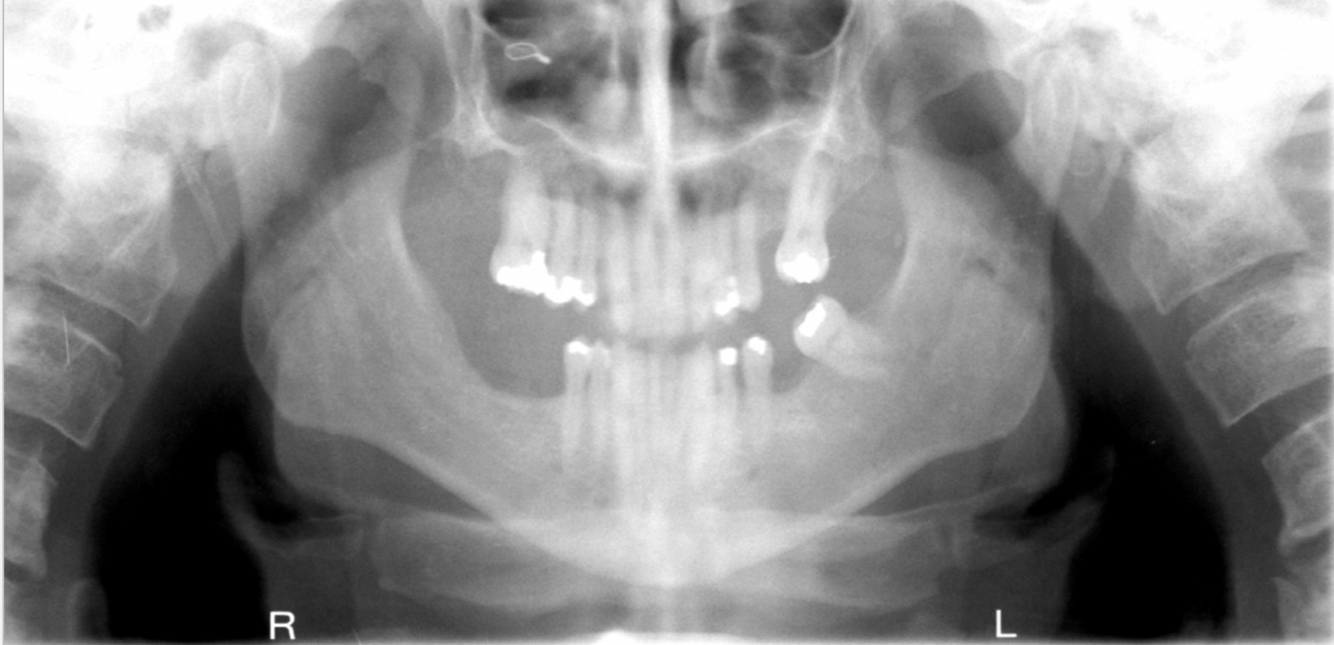

What errors can be seen in the following radiograph? What is the cause of these errors?

A

1. Anterior teeth are narrowed and blurred

2. Cervical spine is superimposed on ramus ( double real image of cervical spine)

Cause: Too far forward